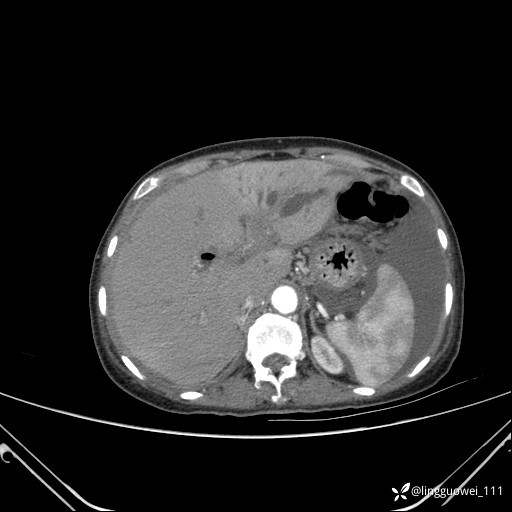

病例女,65岁,门诊行胃肠镜检查后,说腹胀入院检查,CT能发现病因吗?已公布结果

主诉:门诊行胃肠镜检查后,诉腹胀,入院检查,肝有病变吗?腹膜及腹腔的表现有特征性吗?

平扫:

增强动脉期:

门脉期:

延迟期: